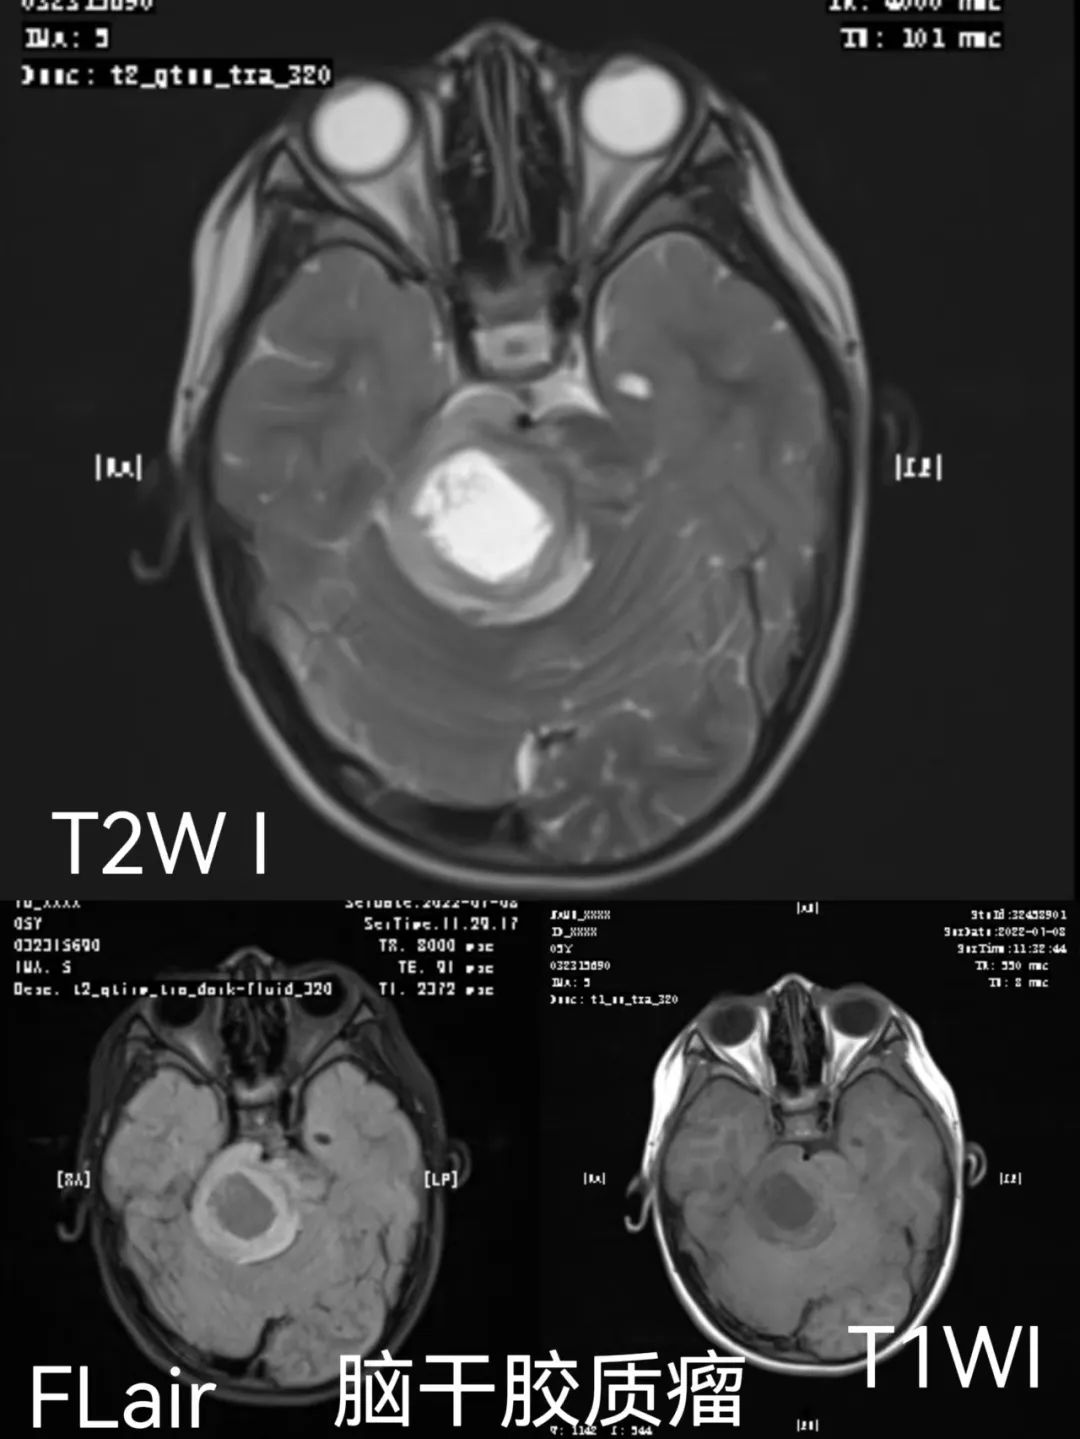

渭南市妇幼保健院CT&MRI室装备有西门子公司16排螺旋CT机一台及西门子1.5T核磁共振一台。开展的诊查项目包括全身各部位CT检查,磁共振全身各部位的平扫及部分部位的增强检查(颅脑增强、乳腺增强、垂体增强、上腹部及盆腔增强),磁共振血管成像(MRA)、磁共振胰胆管成像(MRCP)、磁共振尿路成像(MRU)、全脊柱成像等,为临床科室的治疗方案提供了可靠依据。本科室长期聘请西安儿童医院教授指导工作,及时为疑难患者会诊,使群众更加方便享受到上级医院专家的医疗服务。近两年来在教授的指导下,提高了科室的整体诊断水平,尤其是在儿童颅脑先天性疾病及中枢系统疾病方面有了显著的提高,更加突出妇幼的特色。

放射"摄影作品"